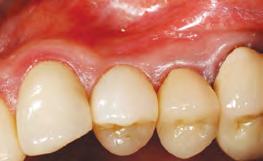

1. Pre-operative assessment demonstrates minimal zone and thickness of buccal keratinized gingiva, with a medium periodontal phenotype.

2. Pre-operative CBCT with virtually planned implant placement. A thin buccal plate (<1mm) is measured. Good apical bone is noted for the placement of a Straumann® 12mmx4.1mm bone level tapered implant.